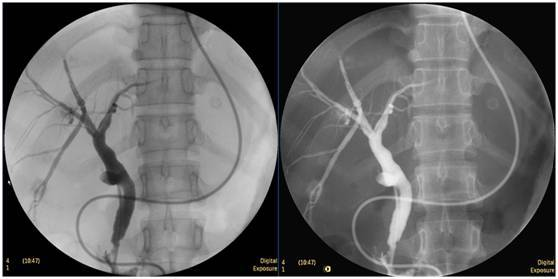

鼻膽管造影

立位注入造影劑,膽總管顯影好,稍擴張,未見結石影。

膽總管結石

柱狀球囊擴張完全,膽總管擴張,下段見充盈缺損影。

膽總管擴張,下段見明顯充盈缺損(上圖為反片且局部放大后效果)